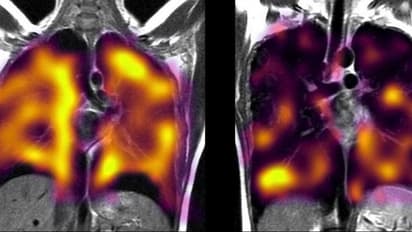

കൊവിഡ് വന്ന് ഭേദമായ ശേഷവും ദീർഘനാളായി രോഗലക്ഷണങ്ങളുള്ളവരിലും ശ്വാസകോശ തകരാറുകൾ ഉണ്ടാകാമെന്ന് പുതിയ പഠനം. ഓക്സ്ഫോർഡ് ബയോമെഡിക്കൽ റിസർച്ച് സെന്ററിലെ ശാസ്ത്രജ്ഞർ കൊവിഡിന് ശേഷം ശ്വാസതടസ്സം അനുഭവിക്കുന്നവരുടെ ശ്വാസകോശത്തിലെ അസാധാരണതകൾ കണ്ടെത്താൻ 'സെനോൺ ഗ്യാസ് സ്കാൻ' (xenon gas scan) ഉപയോഗിച്ച് പഠനം നടത്തുകയായിരുന്നു.

പഠനത്തിനായി ഓക്സ്ഫോർഡ്, ഷെഫീൽഡ്, കാർഡിഫ്, മാഞ്ചസ്റ്റർ എന്നിവിടങ്ങളിൽ നിന്നുള്ള സംഘം സെനോൺ ഗ്യാസ് സ്കാനുകളും മറ്റ് ശ്വാസകോശ പ്രവർത്തന പരിശോധനകളും മൂന്ന് ഗ്രൂപ്പുകളിലായി താരതമ്യം ചെയ്തു. സിടി സ്കാനുകൾ ഉൾപ്പെടെയുള്ള മറ്റ് പരിശോധനകൾ നടത്തിയിട്ടും രോഗികളിൽ ശ്വാസകോശത്തിൽ നിന്ന് രക്തത്തിലേക്ക് വാതക കൈമാറ്റം ഗണ്യമായി കുറഞ്ഞതായി പഠനത്തിന്റെ പ്രാരംഭ ഫലങ്ങൾ സൂചിപ്പിക്കുന്നതായി ഗവേഷകയായ ഡോ. എമിലി ഫ്രേസർ ബിബിസിയോട് പറഞ്ഞു.

എക്സ്-റേയും സിടി സ്കാനും ഉപയോഗിച്ച് ശ്വാസതടസ്സത്തിന്റെ ക്ലിനിക്കൽ കാരണങ്ങൾ കണ്ടെത്താനാകാതെ നിരാശയിൽ നിന്നാണ് പഠനം നടത്തിയതെന്ന് ഡോ. എമിലി ഫ്രേസർ പറഞ്ഞു. പ്രൊഫ. ജിം വൈൽഡും ഷെഫീൽഡ് സർവകലാശാലയിലെ പൾമണറി, ലംഗ് ആൻഡ് റെസ്പിറേറ്ററി ഇമേജിംഗ് ഷെഫീൽഡ് (പോളാരിസ്) ഗവേഷണ ഗ്രൂപ്പും ചേർന്നാണ് ഈ രീതിയും ക്ലിനിക്കൽ ആപ്ലിക്കേഷനുകളും വികസിപ്പിച്ചെടുത്തത്.